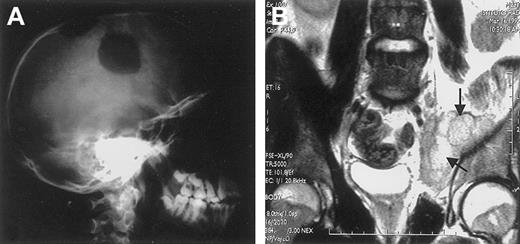

ALK+ ALCL mostly occurs in the first 3 decades of life (Figure 9),40,69,101,133,135with male predominance being particularly striking in the second and third decades of life (male/female ratio 6.5).133 This lymphoma frequently presents as an aggressive stage III to IV disease, usually associated with systemic symptoms (75%), especially high fever.133 Extranodal involvement is frequent (60%), with approximately 40% of patients showing 2 or more extranodal sites of the disease. In a large study,133 the frequency of extranodal sites of lymphoma involvement was as follows: skin 21%, bone (solitary or multiple lesions) 17% (Figure 10), soft tissues 17% (Figure 10), lung 11%, and liver 8%, with involvement of the gut and central nervous system (CNS) being a rare event. The incidence of bone marrow involvement is approximately 11% when analyzed with hematoxylin and eosin stains and approximately 30% when checked with immunohistochemistry because scattered ALCL cells are detectable in bone marrow trephines only when they are specifically labeled.134

Extranodal involvement in ALK+ ALCL.

(A) Large osteolytic lesions of the skull in a 14-year-old boy. (B) Involvement of the right obturator muscle (arrows) in a 25-year-old man.